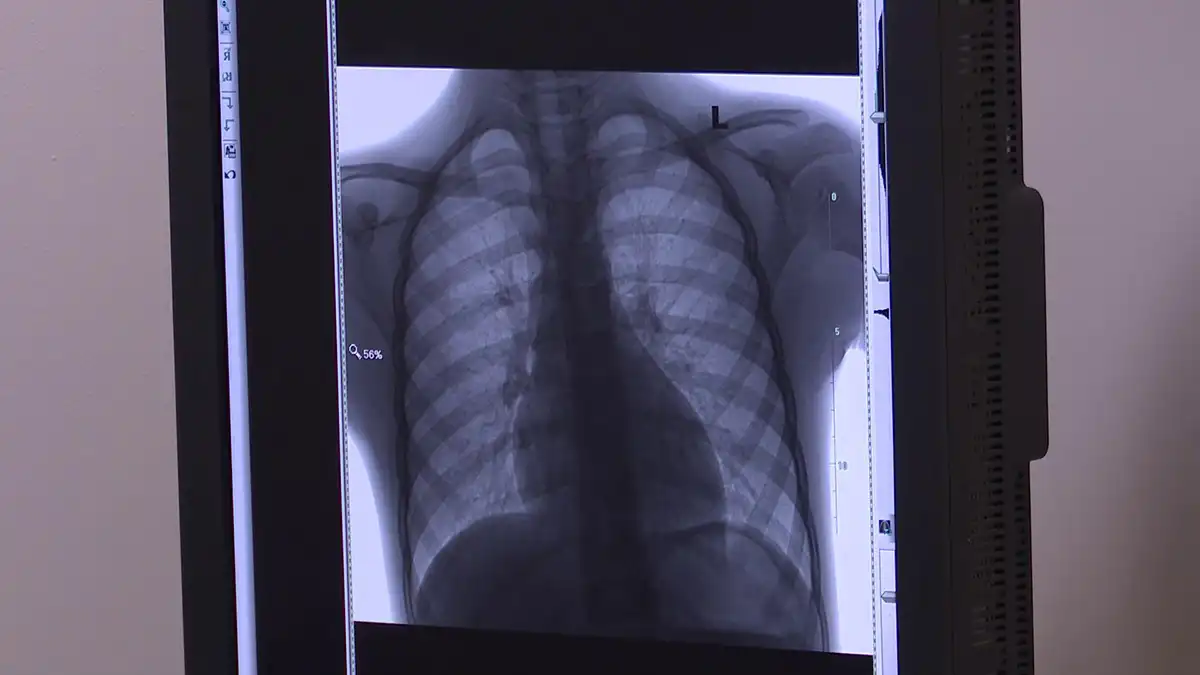

Өлкәннәр арасында туберкулез профилактика тикшеренүе вакытында раслана. Белгечләр ассызыклавынча, күпчелеге флюорографияне вакытында узмаган. Бу вакытта инде ул чирне әйләнә-тирәдәгеләргә дә йоктырып өлгергән була.

Бөтендөнья туберкулезга каршы көрәш ункөнлеге кысаларында үзәк базарда күчмә флюоромобиль эшли. Ел да якынча 15 мең кешене тикшерәләр. Туберкулез һава аша йога. Моның өчен авыру кешенең бер тапкыр төчкерүе дә җитә, ди табиблар.